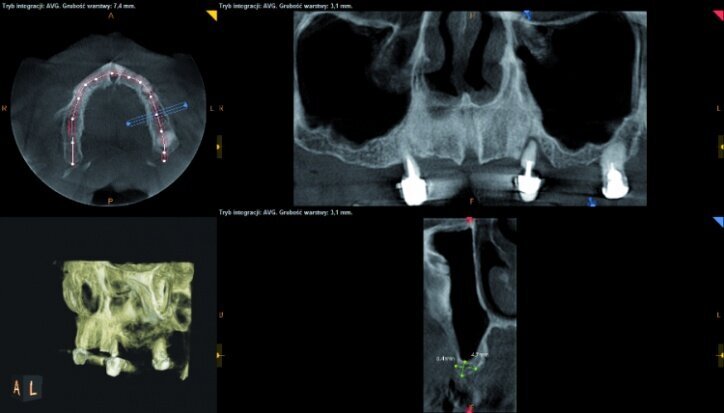

During the process of treatment planning, a few proposals for prosthetic solutions were presented, including permanent and temporary restorations, based on existing teeth as well as implants of various combinations. After analysing CBCT scans (Figs. 3–6) it could be concluded that implantological treatment may be performed at the front maxilla without any additional procedures, however, due to significant atrophy in the lateral part and a low-lying fundus of the left and right maxillary sinus, it appeared necessary to perform augmentation procedures (sinus lift), in order to make implantation possible.